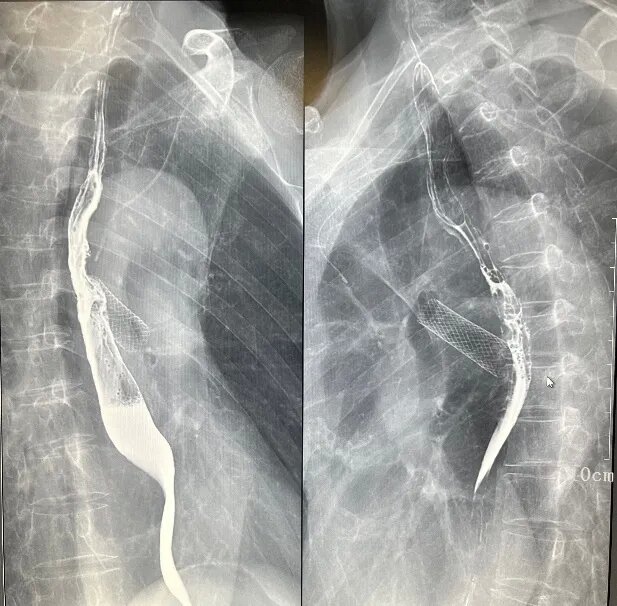

(一)食道鋇劑造影

數字胃腸透視機食道造影